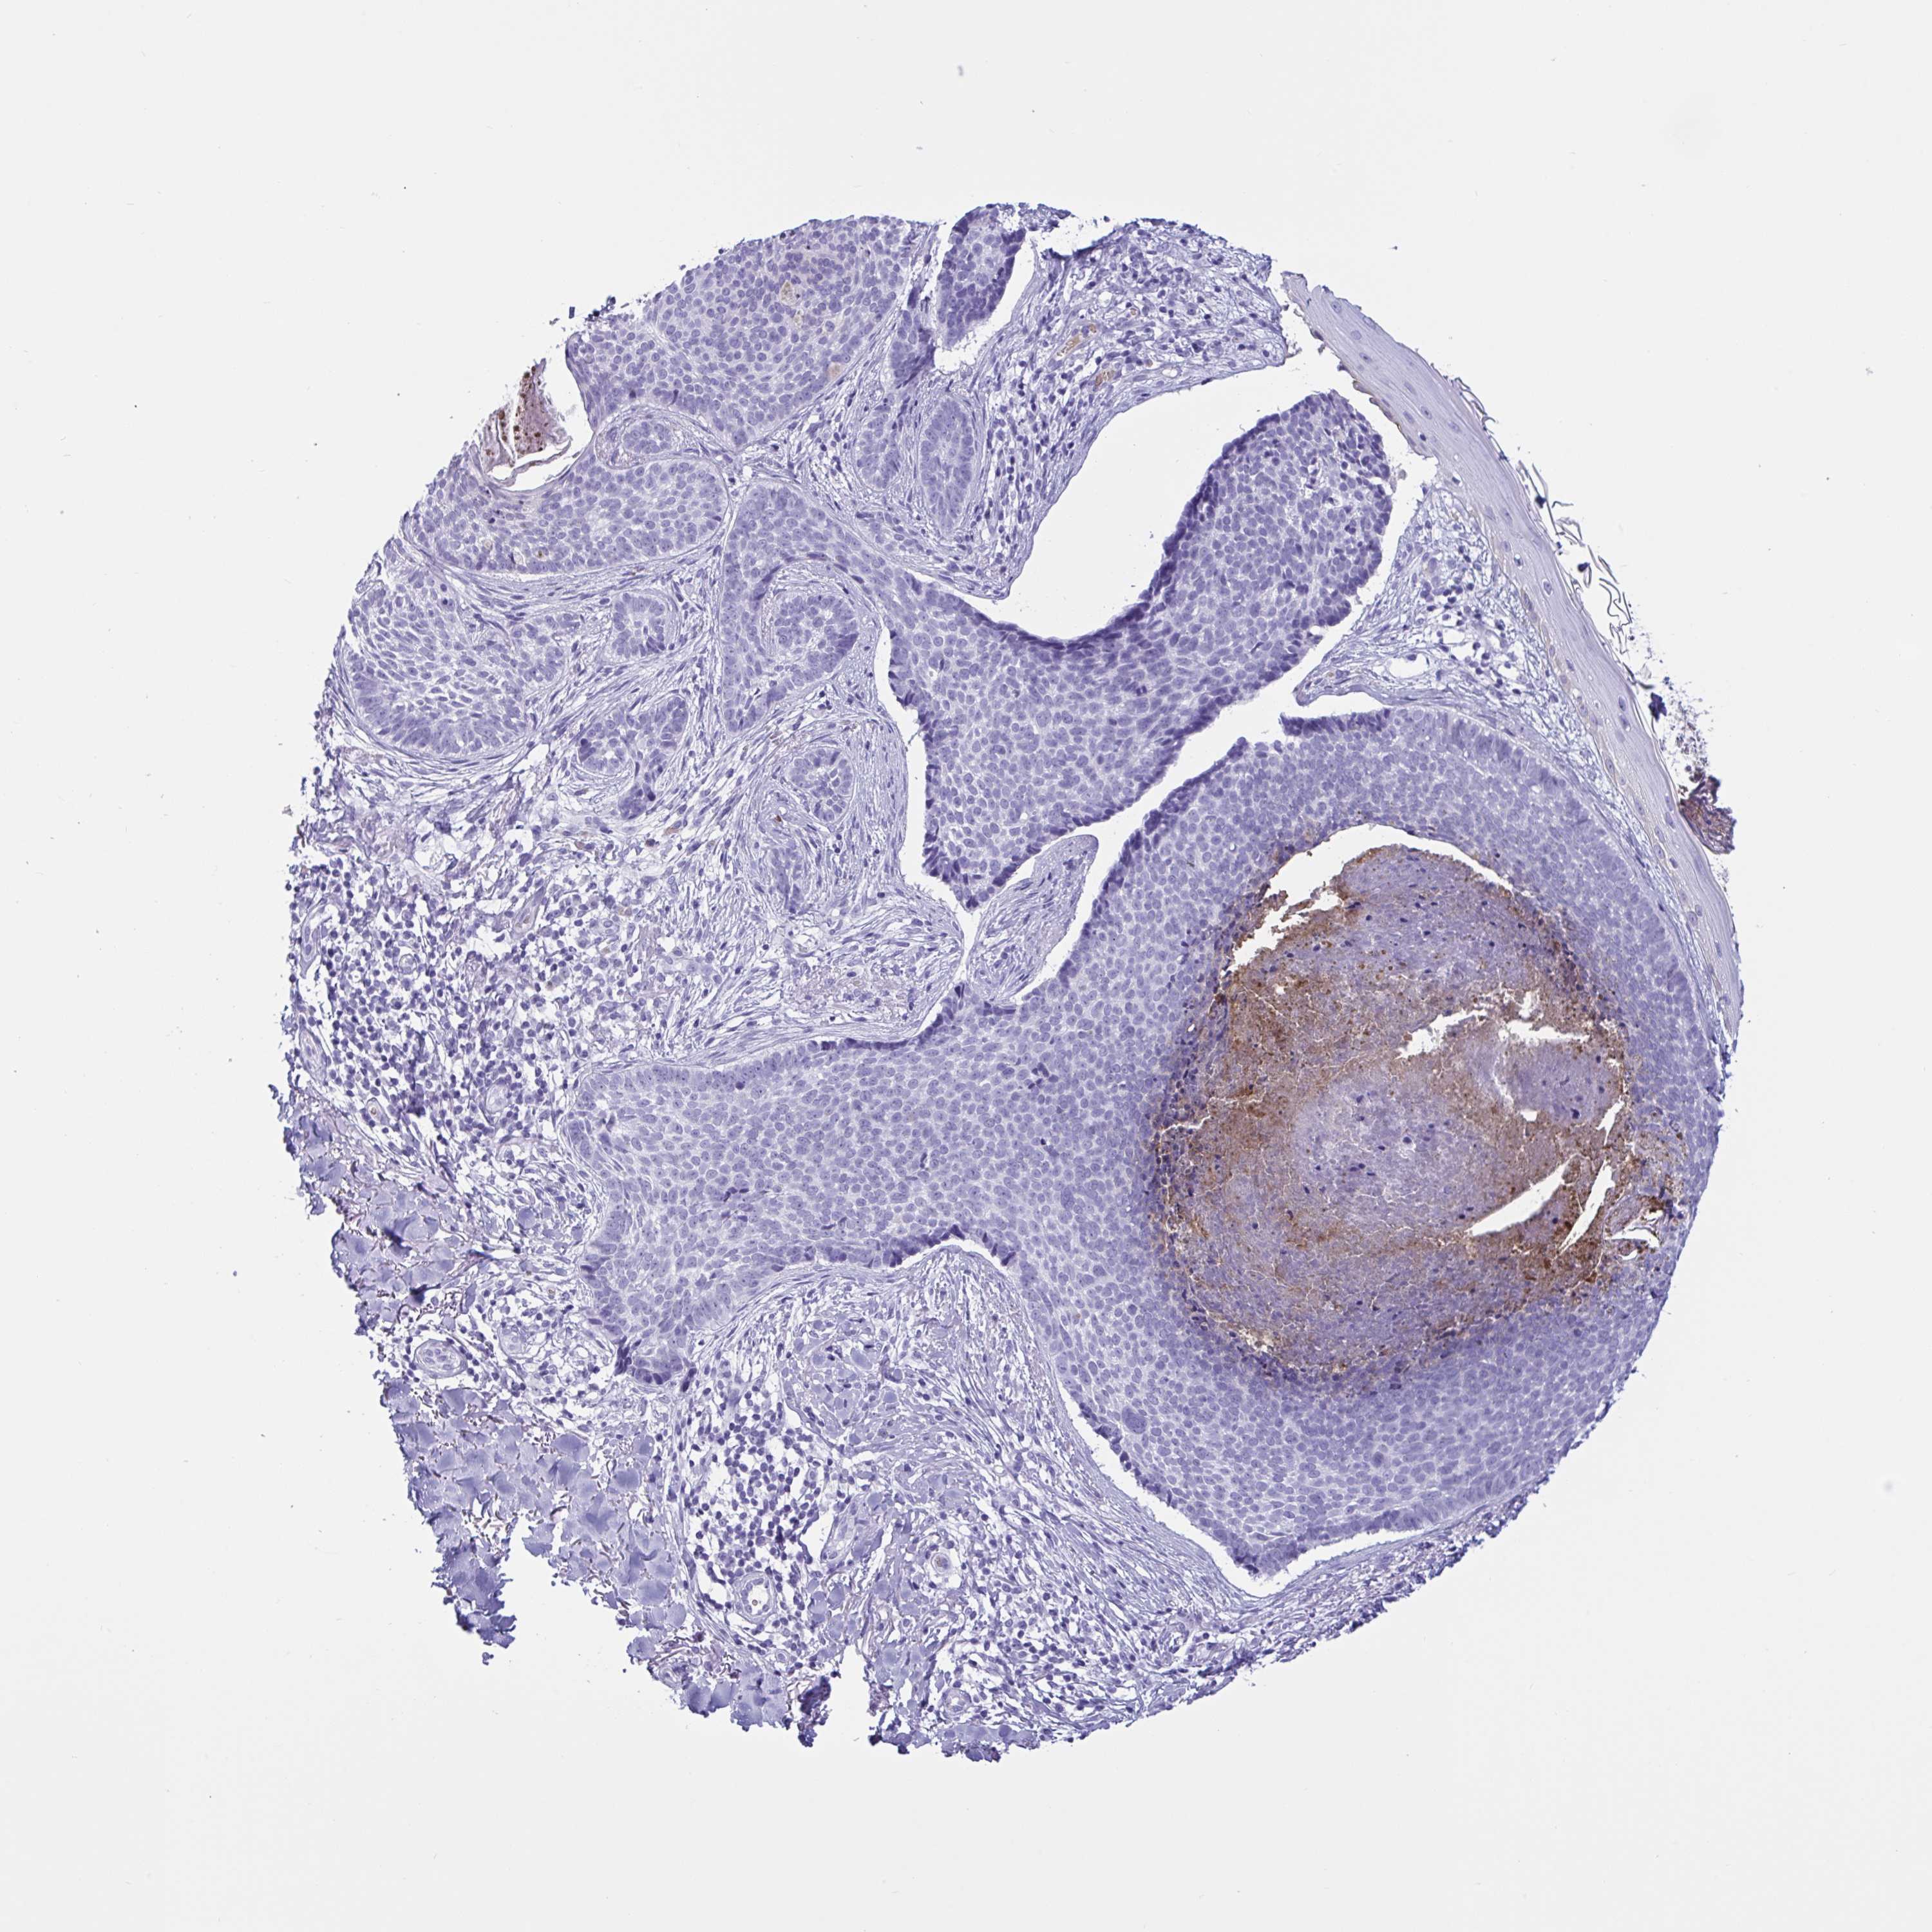

SKIN CANCER - Protein expressioni

A mouse-over function shows sample information and annotation data. Click on an image to view it in a full screen mode. Samples can be filtered based on level of antibody staining by selecting one or several of the following categories: high, medium, low and not detected. The assay and annotation is described here.

Each image is clickable and will lead to virtual microscopy that enables deeper exploration of all samples and also displays staining intensity scores, fraction scores and subcellular localization as well as patient and tissue information for each sample.

Antibody HPA031345

Antibody HPA058494

Antibody CAB002759

Basal cell carcinoma